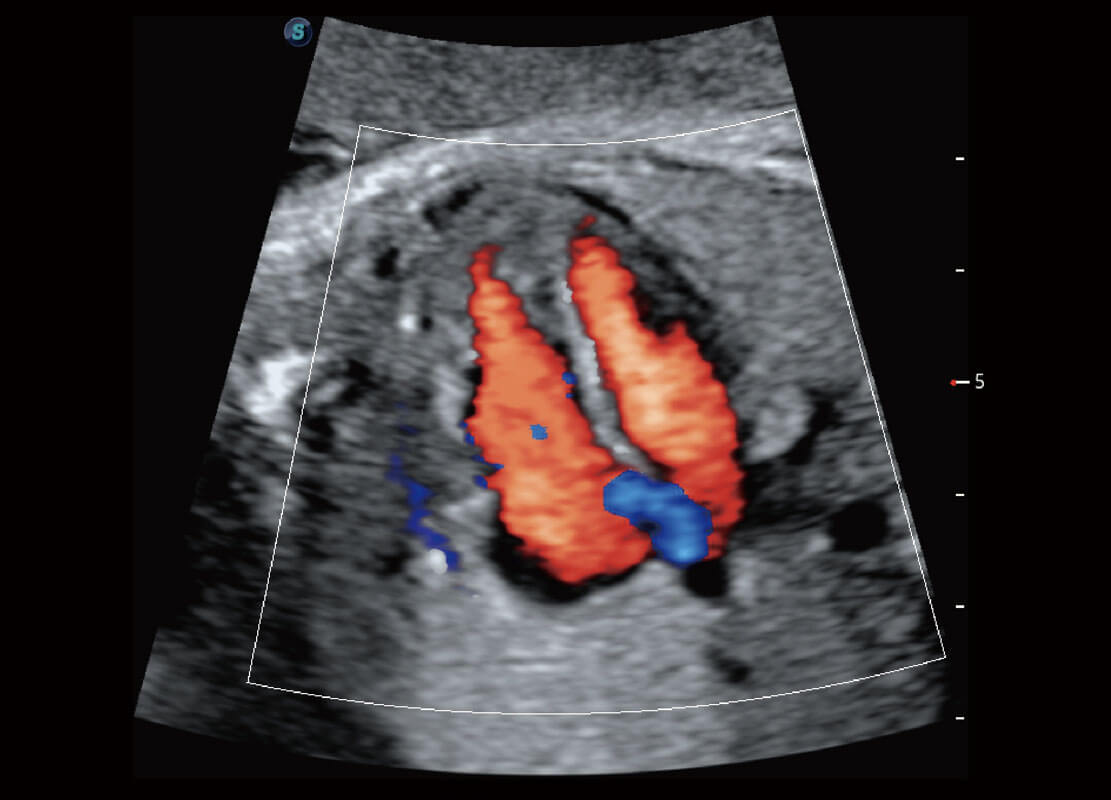

早孕-胎心

胎儿体循环